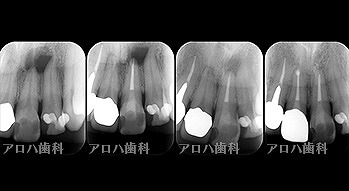

透過像が消失したケース

case1

初回根管治療

1年予後

治療回数1回

case2

左の透過像の変化(5年予後)

(のちに右も壊死により根管治療)

case3

再根管治療

瘻孔の消失

case4

再根管治療 2年予後

再根管治療の汚染の改善

破折器具除去もあり。